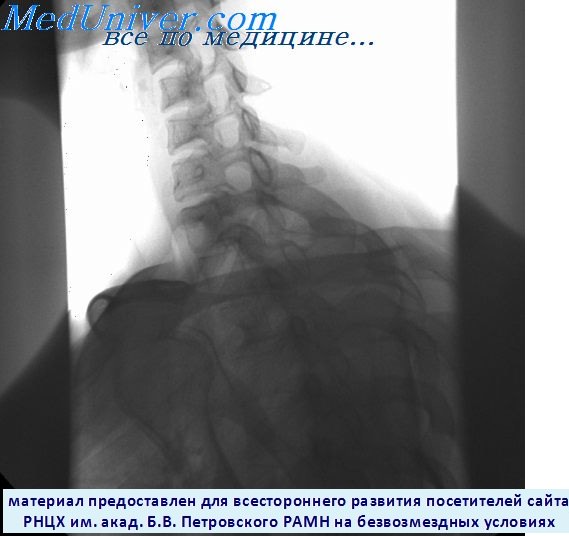

Медицина и диагностика: Аномалии ребер на рентгене